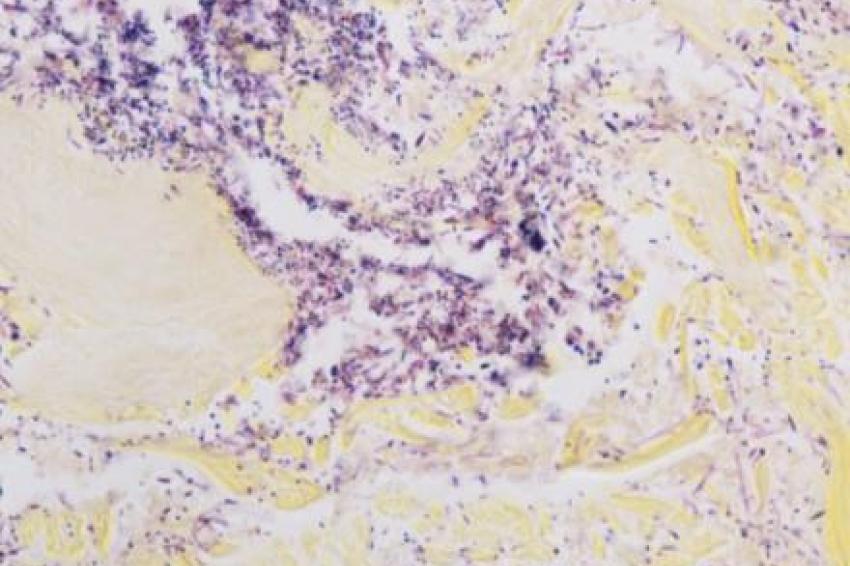

Das neue vollautomatische Gram-Färbekit für das Färbesystem VENTANA BenchMark Special Stains unterstützt Pathologen, in fixierten Gewebeproben Gram-positive und Gram-negative Bakterien zu unterscheiden. Der klinische Nutzen dieser Klassifikation mittels der Gram-Färbung liegt darin, einen ersten Hinweis auf den Infektionstyp eines Patienten zu erhalten.

Die Gram-Färbung gehört zu einer Reihe histochemischer Spezialfärbungen, die in vielen Laboren auch heute noch manuell durchgeführt werden. Mit der Automatisierung der Färbung bietet Roche Diagnostics den Anwendern eine effiziente und sichere Methode, diese technisch herausfordernde Untersuchung durchzuführen. Dies ermöglicht eine höhere Produktivität, größere Reproduzierbarkeit und bessere Qualität der Testung.

"Mit dem neuen Gram-Färbekit profitieren unsere Kunden von einer einheitlichen und klaren Darstellung, wie sie bei der manuellen Gram-Färbung selten erreicht wird. Auch dieses neue Produkt spiegelt unser stetiges Engagement für Qualität und das Vorantreiben einer standardisierten Diagnostik mittels erstklassiger Automatisierung wider", betont Michael Götzl.